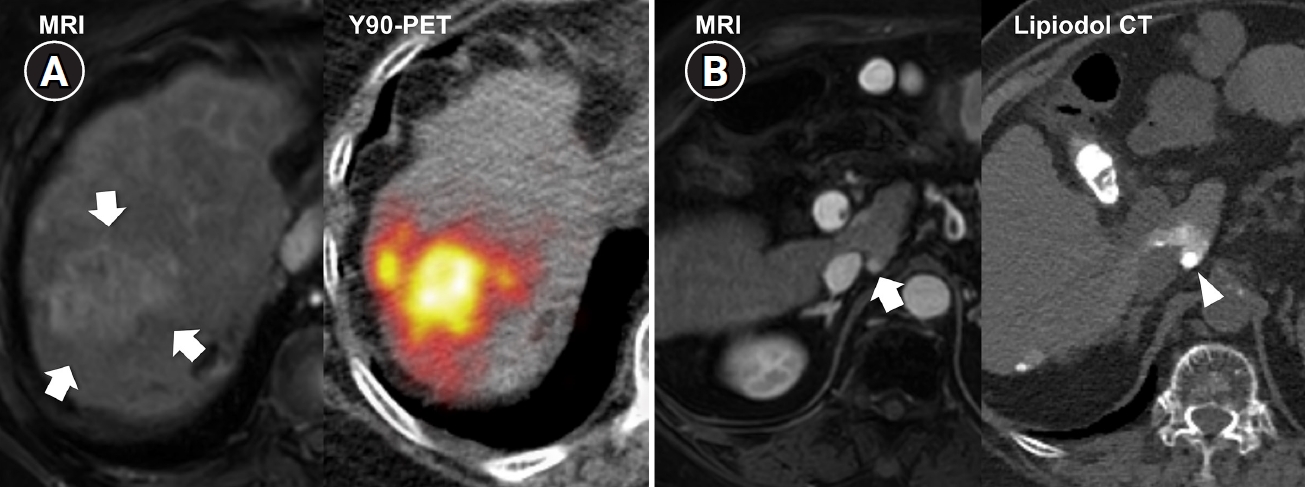

Fig. 3.

Central bile duct injury after transarterial radioembolization in an 80-year-old woman with ruptured hepatocellular carcinoma. (A) Computed tomography obtained 5 months after selective infusion of Y-90 microspheres via A1, A4, and A8 shows extensive radiation necrosis (arrows) in segments 4 and 8, with dilatation of the intrahepatic bile ducts (circle) in the left lateral segments. (B) Because of progressive jaundice and pruritus, percutaneous transhepatic biliary drainage was performed, and cholangiography showed segmental occlusion of the left main bile duct (arrow), suggesting radiation-induced ductal injury.

From a procedural standpoint, TARE also presents inherent technical challenges. Unlike conventional TACE, in which chemoembolic materials are radiopaque and their distribution can be continuously observed under fluoroscopy, Y-90 microspheres are invisible during infusion, making real-time monitoring impossible [13]. Although a technetium-99m–labeled macroaggregated albumin (99mTc-MAA) scan is performed pre-procedurally to simulate microsphere distribution, actual flow dynamics during treatment may differ, often resulting in a wider-than-anticipated infusion territory and unintended radiation exposure to non-tumorous liver parenchyma. This unpredictability can contribute to hepatotoxicity or even REILD, particularly when the functional liver reserve is marginal. In addition, for central or hilar lesions, the inability to monitor microsphere flow raises another critical concern. When excessive embolic effect occurs in fine caudate or peribiliary arteries, flow stasis cannot be detected in real time, leading to prolonged high-dose radiation exposure to the peribiliary plexus and subsequent central bile duct injury [32] (Fig. 3). Therefore, achieving a truly selective and controlled infusion is technically more challenging with TARE than with TACE, where the infusion of chemoembolic materials can be directly visualized and adjusted during the procedure. These limitations underscore a fundamental difference between the two modalities: whereas TACE allows dynamic control and immediate correction of reflux or over-embolization, TARE relies entirely on pre-procedural planning and hemodynamic prediction, making the actual treatment field less predictable and inherently less selective.